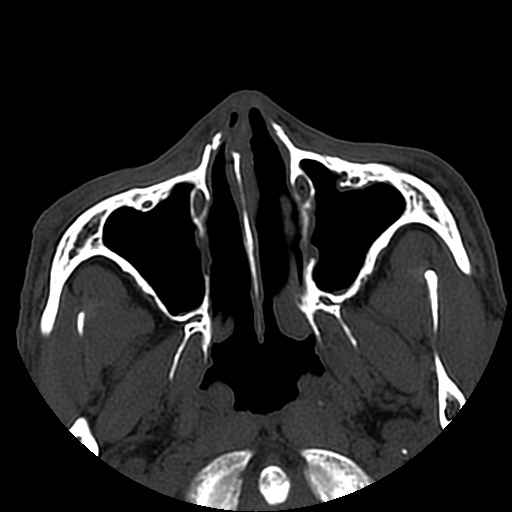

以下是引用liaoqiang在2008-7-16 21:15:00的发言:[br]右侧鼻骨骨折

以下是引用zxd95在2008-7-16 21:39:00的发言:[br]右侧上颌骨额突骨折。[br][br][br][br]